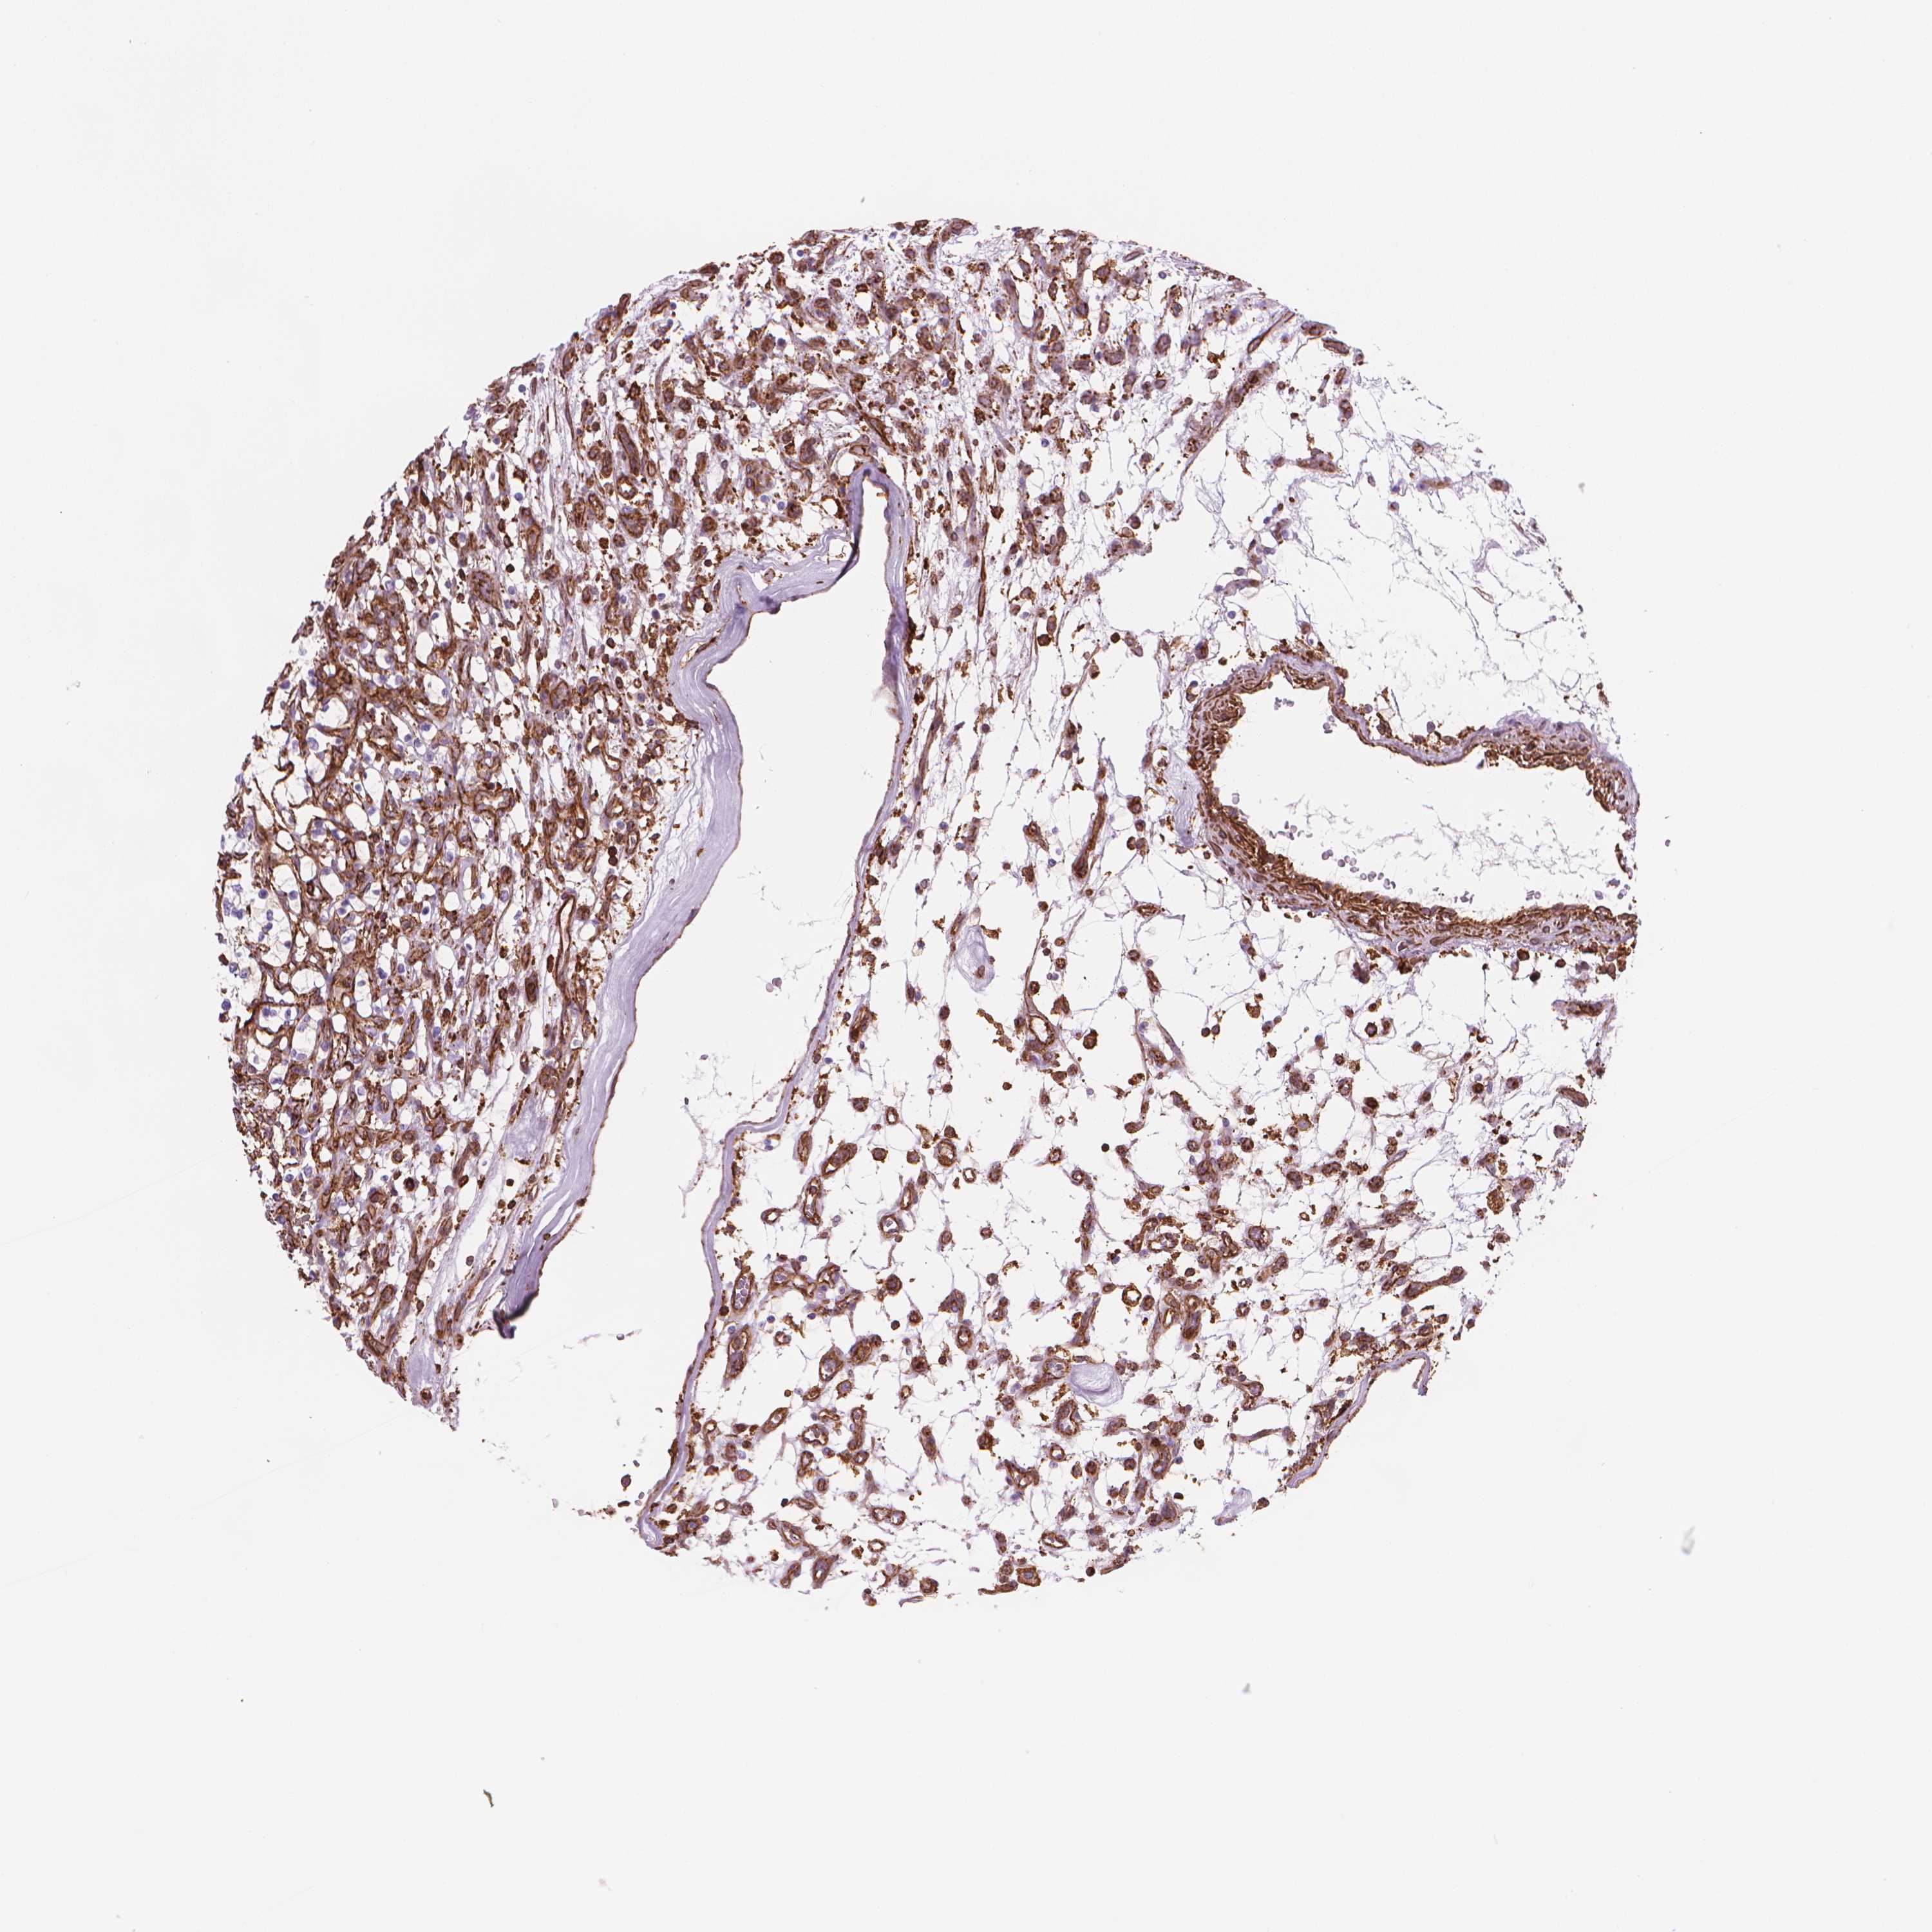

KIDNEY RENAL CLEAR CELL CARCINOMA (VALIDATION) - Interactive survival scatter ploti

The Survival Scatter plot shows the clinical status (i.e. dead or alive) for all individuals in the patient cohort, based on the same data that underlies the corresponding Kaplan-Meier plots. Patients that are alive at last time for follow-up are shown in blue and patients who have died during the study are shown in red.

The x-axis shows the expression levels (FPKM) of the investigated gene in the tumor tissue at the time of diagnosis. The y-axis shows the follow-up time after diagnosis (years). Both axes are complimented with kernel density curves demonstrating the data density over the axes. The top density plot shows the expression levels (FPKM) distribution among dead (red) and alive patients (blue). The right density plot shows the data density of the survived years of dead patients with high and low expression levels respectively, stratified using the cutoff indicated by the vertical dashed line through the Survival Scatter plot. This cutoff is automatically defined based on the FPKM cutoff that minimizes the p-score. The cutoff can be changed by dragging the vertical line or by entering a cutoff value in the square labeled "Current cut-off".

Under the Survival Scatter plot the p-score landscape (black curve; left axis) is shown together with dead median separation (red curve; right axis). Dead median separation is the difference in median mRNA expression between patients who have died with high and low expression, respectively. It is calculated as follows: median FPKM expression of dead patients with high expression - median FPKM expression of dead patients with low expression. This is intended to aid the user in visually exploring custom cutoffs and the associated p-scores and dead median separation.

Individual patient data is displayed and can be filtered by clicking on one or more of the category buttons on the top of the page. Categories describing expression level and patient information include: high, low, alive, dead, female, male and tumor stages. The scale of the x-axis can be toggled between linear and log-scale by clicking on the "x log" button. Mouse-over function shows TCGA ID, patient information and mRNA expression (FPKM) for each patient.

& Survival analysisi

Kaplan-Meier plots summarize results from analysis of correlation between mRNA expression level and patient survival. Patients were divided based on level of expression into one of the two groups "low" (under cut off) or "high" (over cut off). X-axis shows time for survival (years) and y-axis shows the probability of survival, where 1.0 corresponds to 100 percent.

PATJ is validated prognostic, high expression is favorable in Kidney Renal Clear Cell Carcinoma (validation)

Best expression cut offi

Based on the FPKM value of each gene, patients were classified into two groups and association between prognosis (survival) and gene expression (FPKM) was examined. The best expression cut-off refers the FPKM value that yields maximal difference with regard to survival between the two groups at the lowest log-rank P-value. Best expression cut-off was selected based on survival analysis .

When clicking on this number, the vertical dashed line indicating cut-off, the interactive survival plot, and the Kaplan-Meier curve will be adjusted to show results based on the best expression cut-off.

: 30.09

TCGA RNA samplesi

RNA-seq data is reported as average FPKM (number Fragments Per Kilobase of exon per Million reads), generated by the The Cancer Genome Atlas (TCGA) .

Normal distribution across the dataset is visualized with box plots, shown as median and 25th and 75th percentiles. Points are displayed as outliers if they are above or below 1.5 times the interquartile range. FPKM values of the individual samples are presented next to the box plot.

Average pTPM 27.8

Number of samples 100